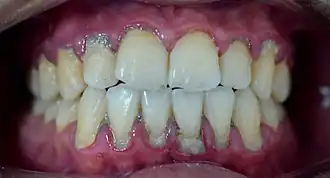

Calculus formation is associated with a number of clinical manifestations, including bad breath, receding gums and chronically inflamed gingiva. Brushing and flossing can remove plaque from which calculus forms; however, once formed, calculus is too hard (firmly attached) to be removed with a toothbrush. Calculus buildup can be removed with ultrasonic tools or dental hand instruments (such as a periodontal scaler).

Plaque accumulation causes the gingiva to become irritated and inflamed, and this is referred to as gingivitis. When the gingiva become so irritated that there is a loss of the connective tissue fibers that attach the gums to the teeth and bone that surrounds the tooth, this is known as periodontitis. Dental plaque is not the sole cause of periodontitis; however it is many times referred to as a primary aetiology. Plaque that remains in the oral cavity long enough will eventually calcify and become calculus.[18] Calculus is detrimental to gingival health because it serves as a trap for increased plaque formation and retention; thus, calculus, along with other factors that cause a localized build-up of plaque, is referred to as a secondary aetiology of periodontitis.